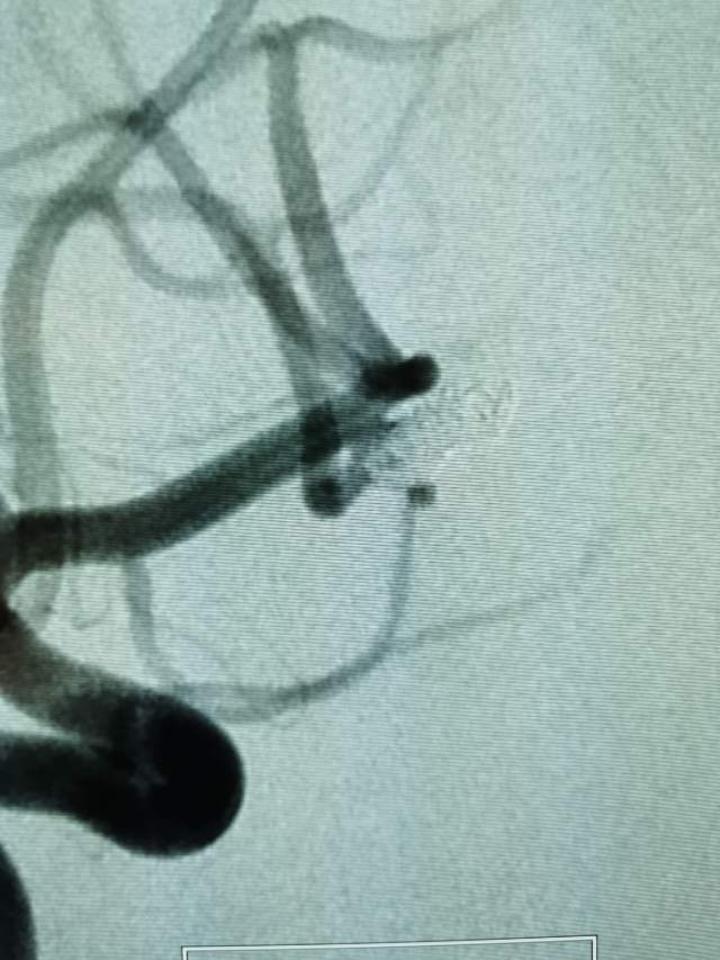

急性期微创介入栓塞破裂的大脑中动脉瘤

急性期栓塞破裂的不规则腊肠状脑动脉瘤